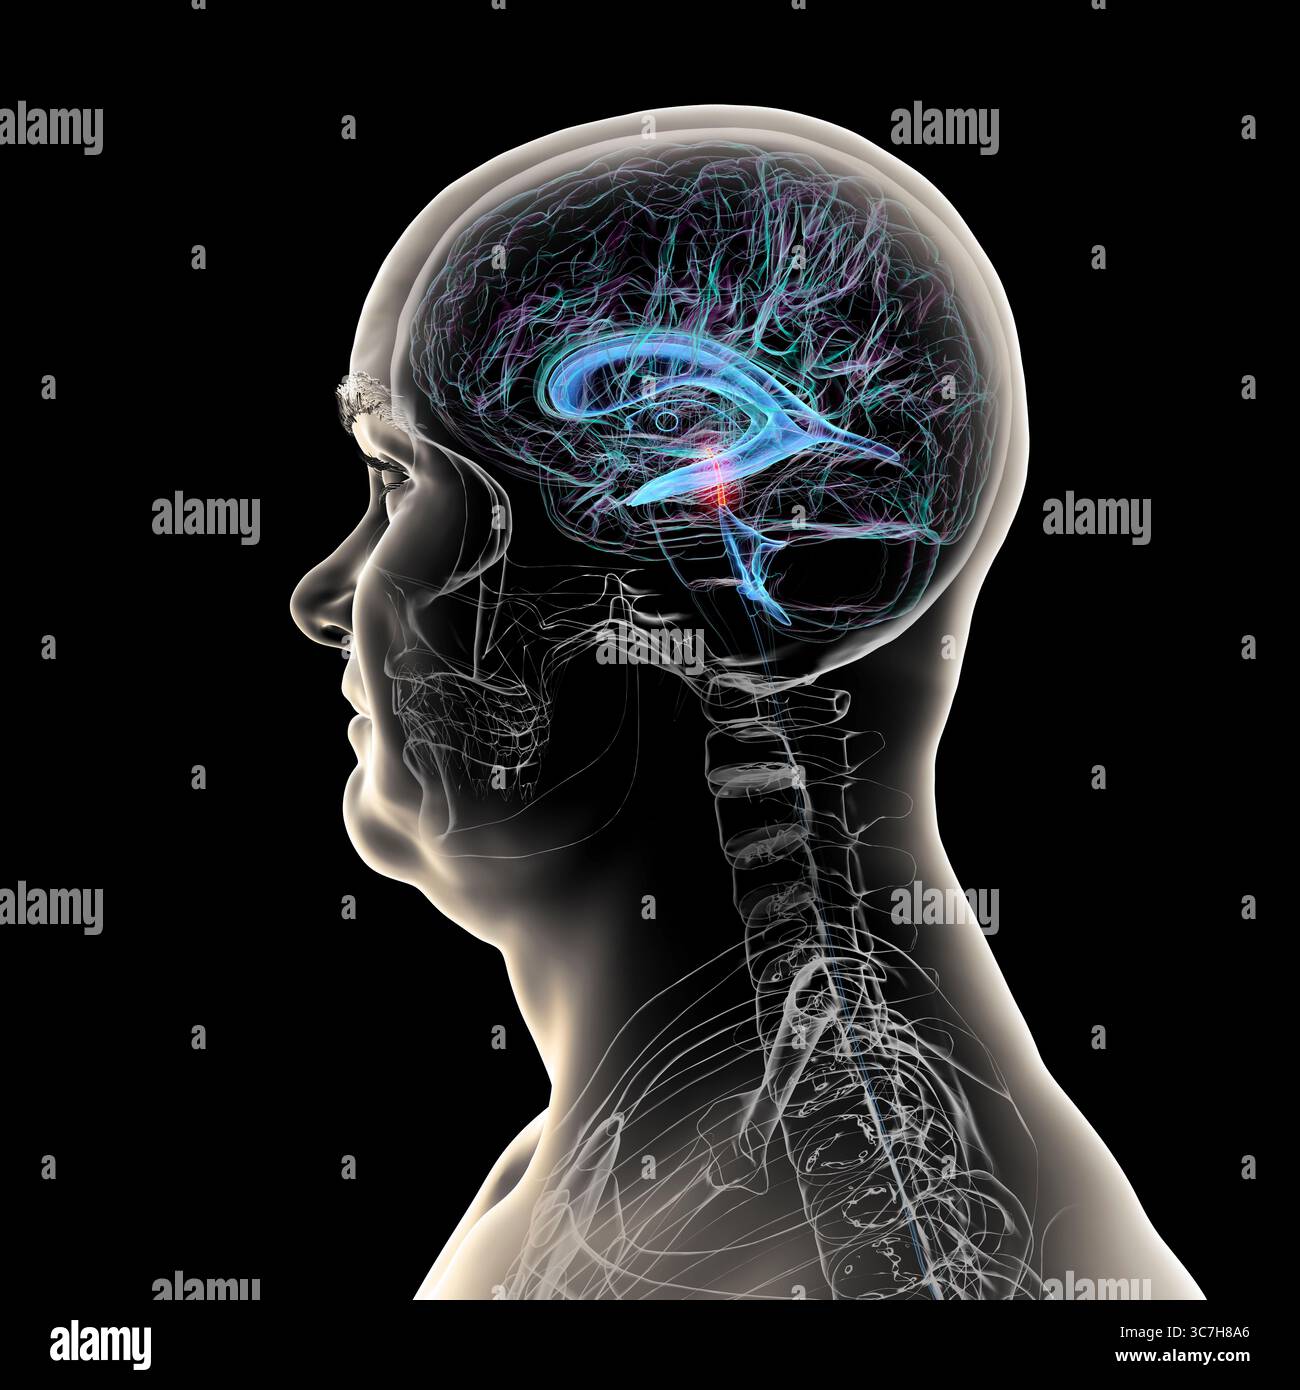

RF3C7H8A8–Abbildung des Gehirns mit hervorgehobenem Aquädukt (rot) und ventrikulärem System (blau), Darstellung des Liquorflusses.

RF3C7H8A6–Abbildung des Gehirns mit hervorgehobenem Aquädukt (rot) und ventrikulärem System (blau), Darstellung des Liquorflusses.

RF3C7H8AA–Abbildung des Gehirns mit hervorgehobenem Aquädukt (rot) und ventrikulärem System (blau), Darstellung des Liquorflusses.

RF3C7H8AF–Abbildung des Gehirns mit hervorgehobenem Aquädukt (rot) und ventrikulärem System (blau), Darstellung des Liquorflusses.

RF3C7H8A3–Abbildung des Gehirns mit hervorgehobenem Aquädukt (rot) und ventrikulärem System (blau), Darstellung des Liquorflusses.